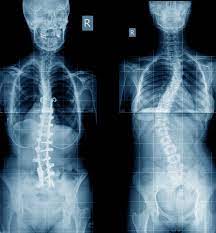

Kyphosis scoliosis / Occipito Cervical Fusion

Spine surgery for kyphosis is recommended for patients whose curvatures continue to progress or cause symptoms despite non-operative treatment. Corrective surgery for thoracic kyphosis is usually recommended when curves are larger than 80° to 90° when measured on x-rays. Kyphosis can extend into the mid or lower back and in those cases surgery is recommended for curves larger than 60° to 70° of kyphosis. Surgery is also an option for patients with disabling back pain or when kyphosis leads to compression of the spinal cord or nerves.

The goal of spinal reconstruction surgery is to decrease the patient's pain and to place the spine in a more natural position. Most commonly this surgery is performed through a posterior approach in the back of the spine. During the surgery, spinal implants including rods and screws are placed next to the spine. These implants correct the spinal deformity and stabilize the spine in its new position while the spine fuses, or mends, together. These bones ultimately heal into one solid piece for spinal stability and prevention of further curve progression. Complications may occur but are not common.